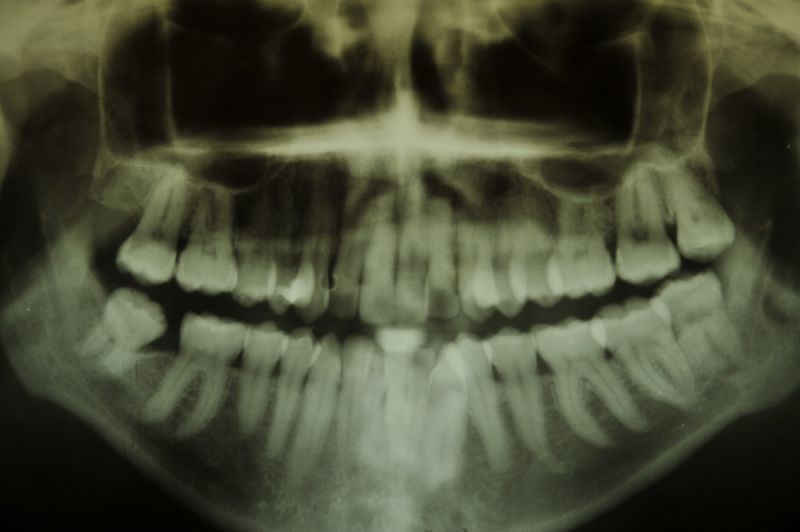

Extreme Dysgnathie einer Patientin aus Kiel mit Aufbissbehelf vollkommen beschwerdefrei

Die Patientin trägt den Aufbissbehelf seit dem 18.09.2014 und ist nach einem Beschwerdelevel "10" vor der Eingliederung des Aufbissbehelfs inzwischen bei Beschwerdelevel "0". Die Patientin kann den Aufbissbehelf auf Grund der "Sperrigkeit" des Geräts bei der Arbeit nicht tragen. Wenn sie den Aufbissbehelf heraus nimmt kommen die Beschwerden nach wenigen Stunden zurück. Wenn sie die Arbeit beendet hat und den Aufbissbehelf einsetzt dauert es ca. 15 Minuten bis wieder Beschwerdefreiheit erreicht ist.